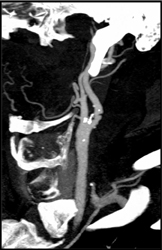

Carotid Stenosis and Plaque